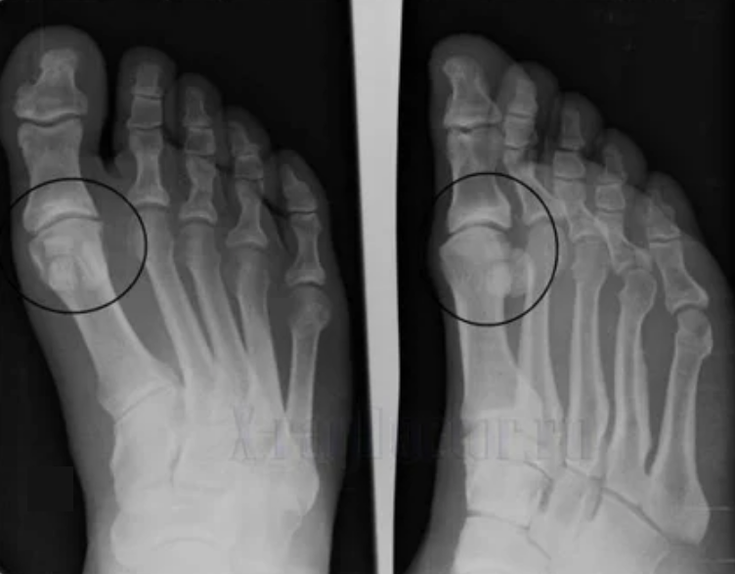

Pour faire un diagnostic, les rhumatologues étudient les plaintes du patient et prescrivent un examen des rayons x. La plupart du temps, la radiographie est utilisée dans 2 projections. Le médecin analyse la présence de troubles de distribution dans le cartilage hyalin et les articulations osseuses. Si l'espace articulaire est réduit, les os sont retardés ou aplatis, il existe des formations kystiques sur la surface du cartilage, les ostéophytes sont des signes évidents d'arthrose. Au cours de l'inspection, l'arthrose indique l'instabilité de l'articulation: l'axe des membres et la subluxation est modifié.

Souvent, une image x ne peut pas fournir des informations complètes sur l'état de l'articulation. Pour une étude plus approfondie, la tomographie informatisée est prescrite, il est efficace d'examiner les os. La résonance magnétique est plus fréquemment utilisée pour étudier les tissus mous.